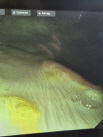

Ein flexibles Endoskop wird in die Nüstern des stehenden Pferdes eingeführt, bis zum Kehlkopf vorgeschoben und dann vom Pferd abgeschluckt. Über die Speiseröhre gelangt man in den Magen. Mithilfe von Luft wird der Magen aufgeweitet, sodass die Magenschleimhaut gut betrachtet und abgebildet werden kann. Außerdem kann man von auffälligen Lokalisationen Proben entnehmen.